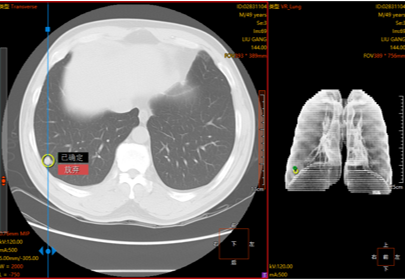

专业级诊断工作站,支持 GPU运算

丰富的高级后处理工具集(持续更新中)

肺部分割